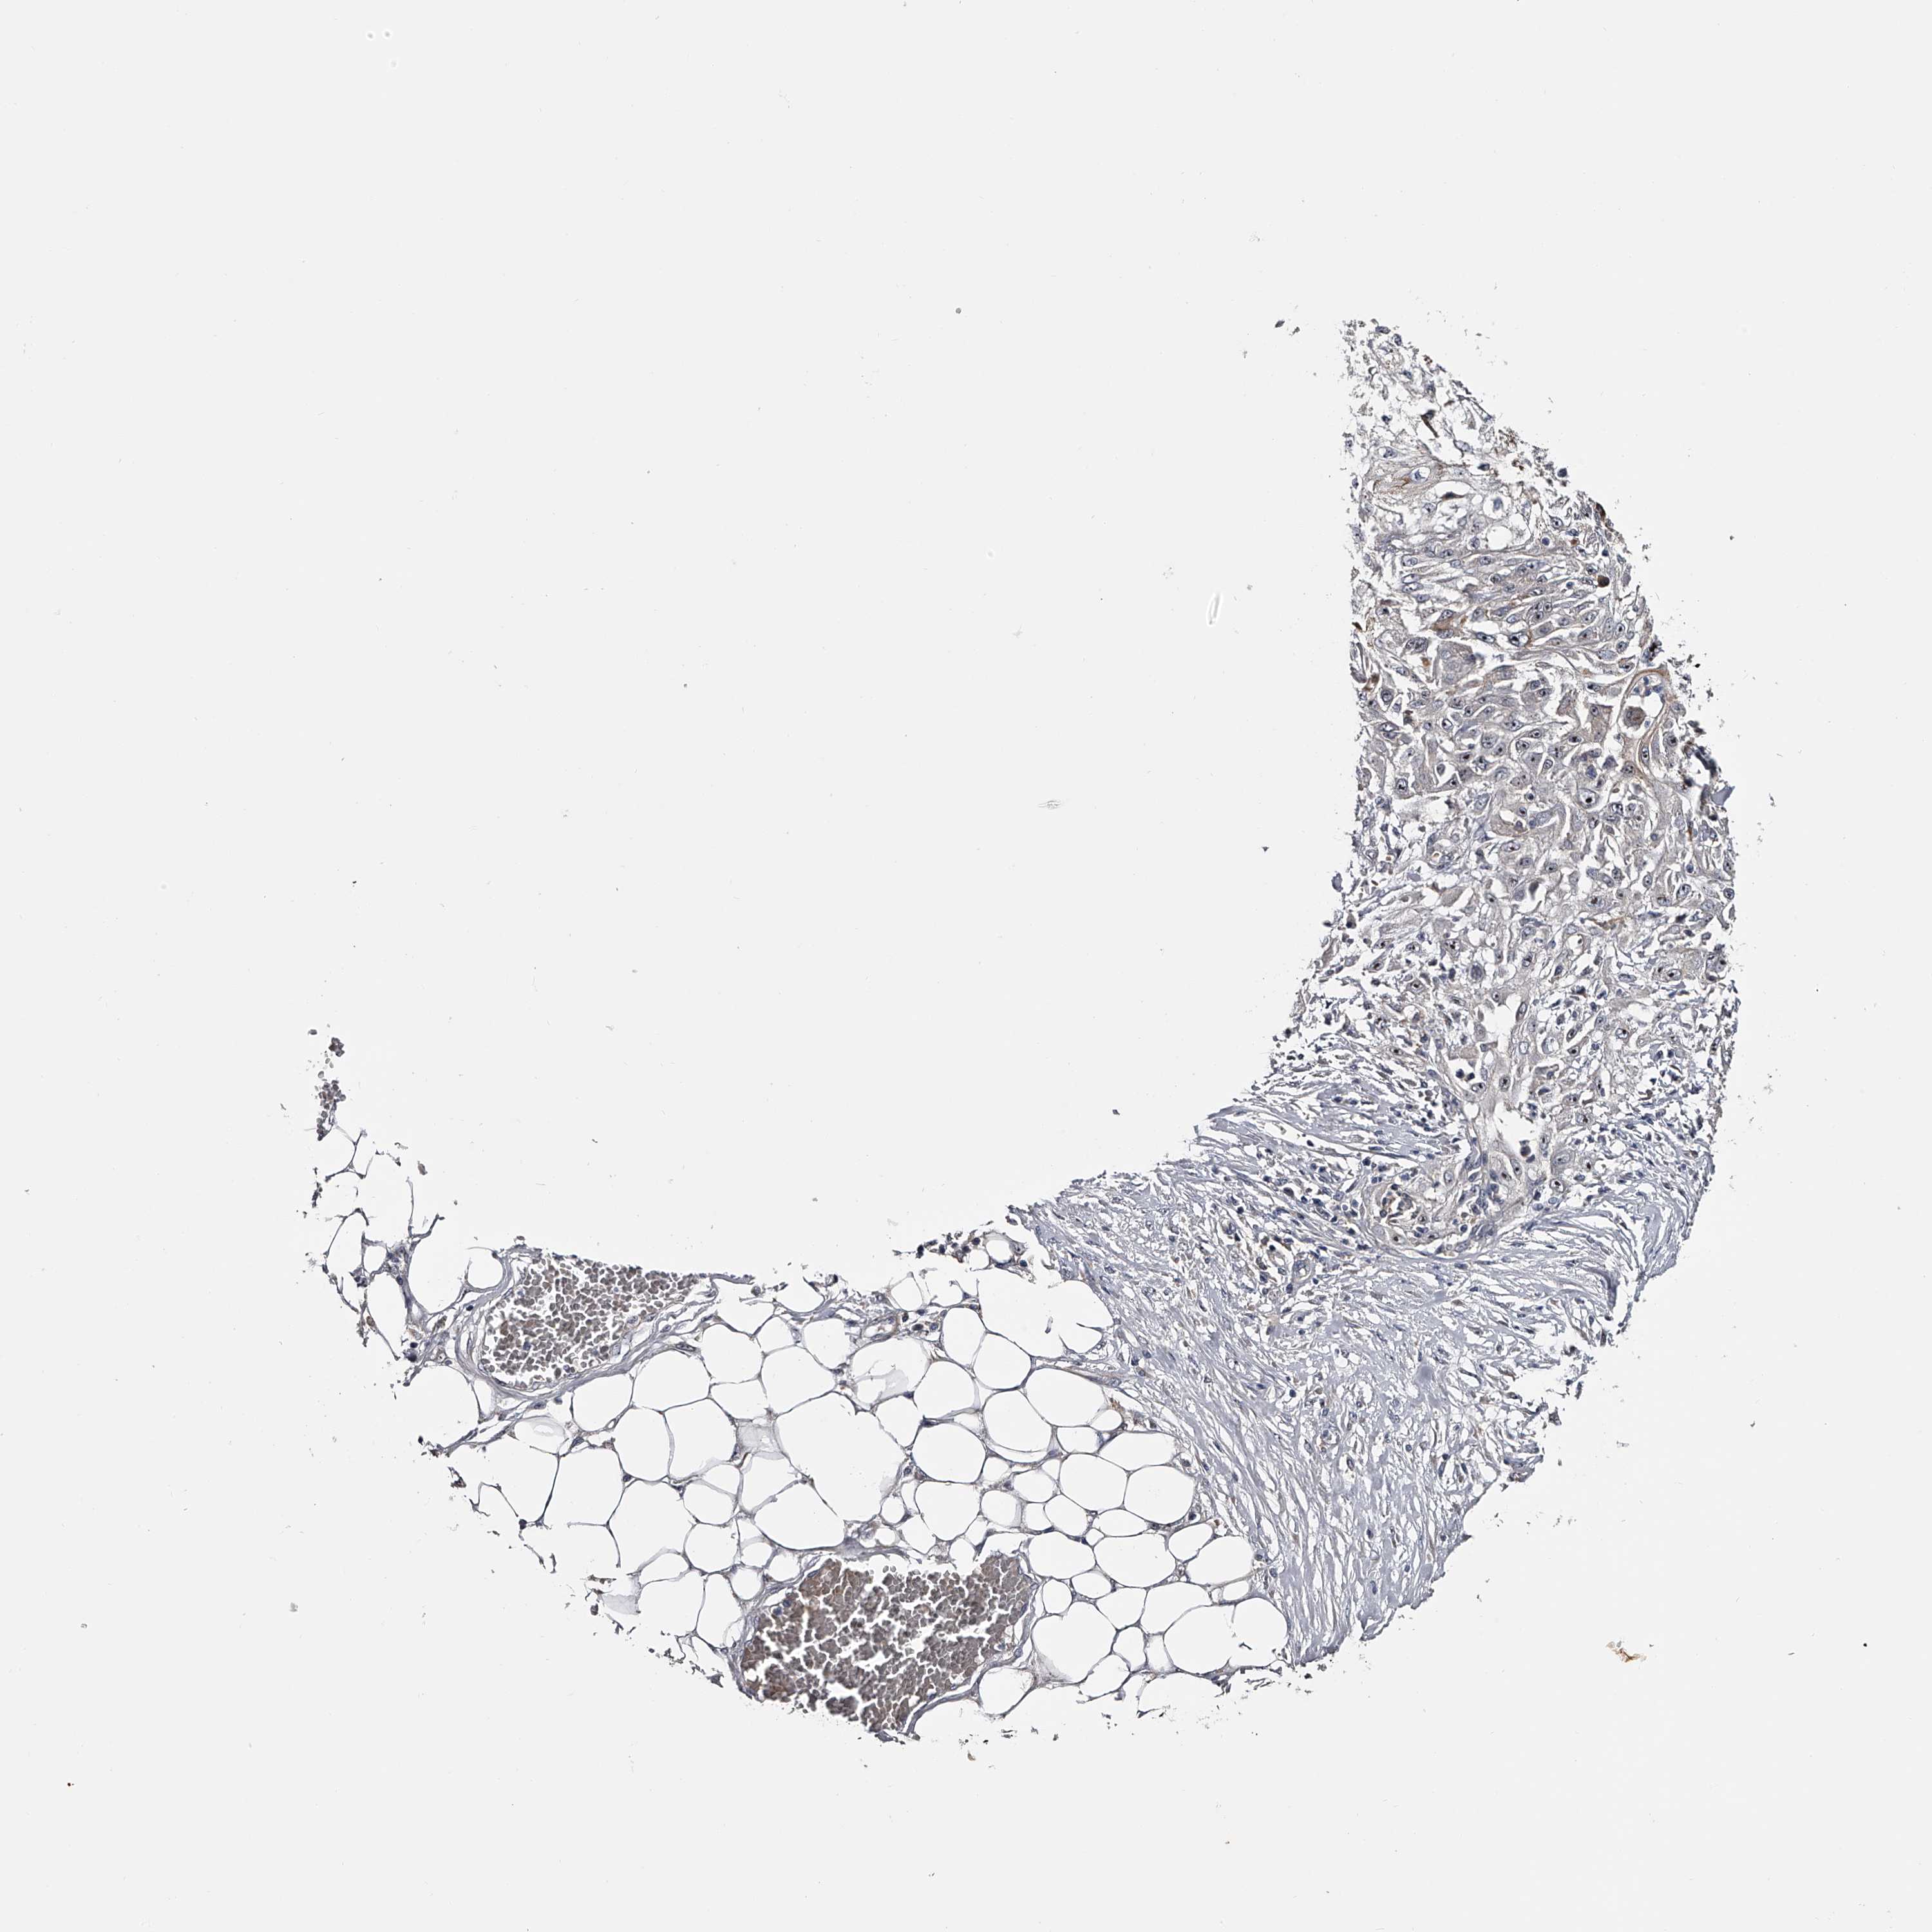

SKIN CANCER - Protein expressioni

A mouse-over function shows sample information and annotation data. Click on an image to view it in a full screen mode. Samples can be filtered based on level of antibody staining by selecting one or several of the following categories: high, medium, low and not detected. The assay and annotation is described here.

Each image is clickable and will lead to virtual microscopy that enables deeper exploration of all samples and also displays staining intensity scores, fraction scores and subcellular localization as well as patient and tissue information for each sample.

Antibody HPA029666

Antibody HPA029667

Antibody HPA029668

Antibody HPA029669

Staining

High

Medium

Low

Not detected

Basal cell carcinoma

Squamous cell carcinoma, NOS

Squamous cell carcinoma, metastatic, NOS